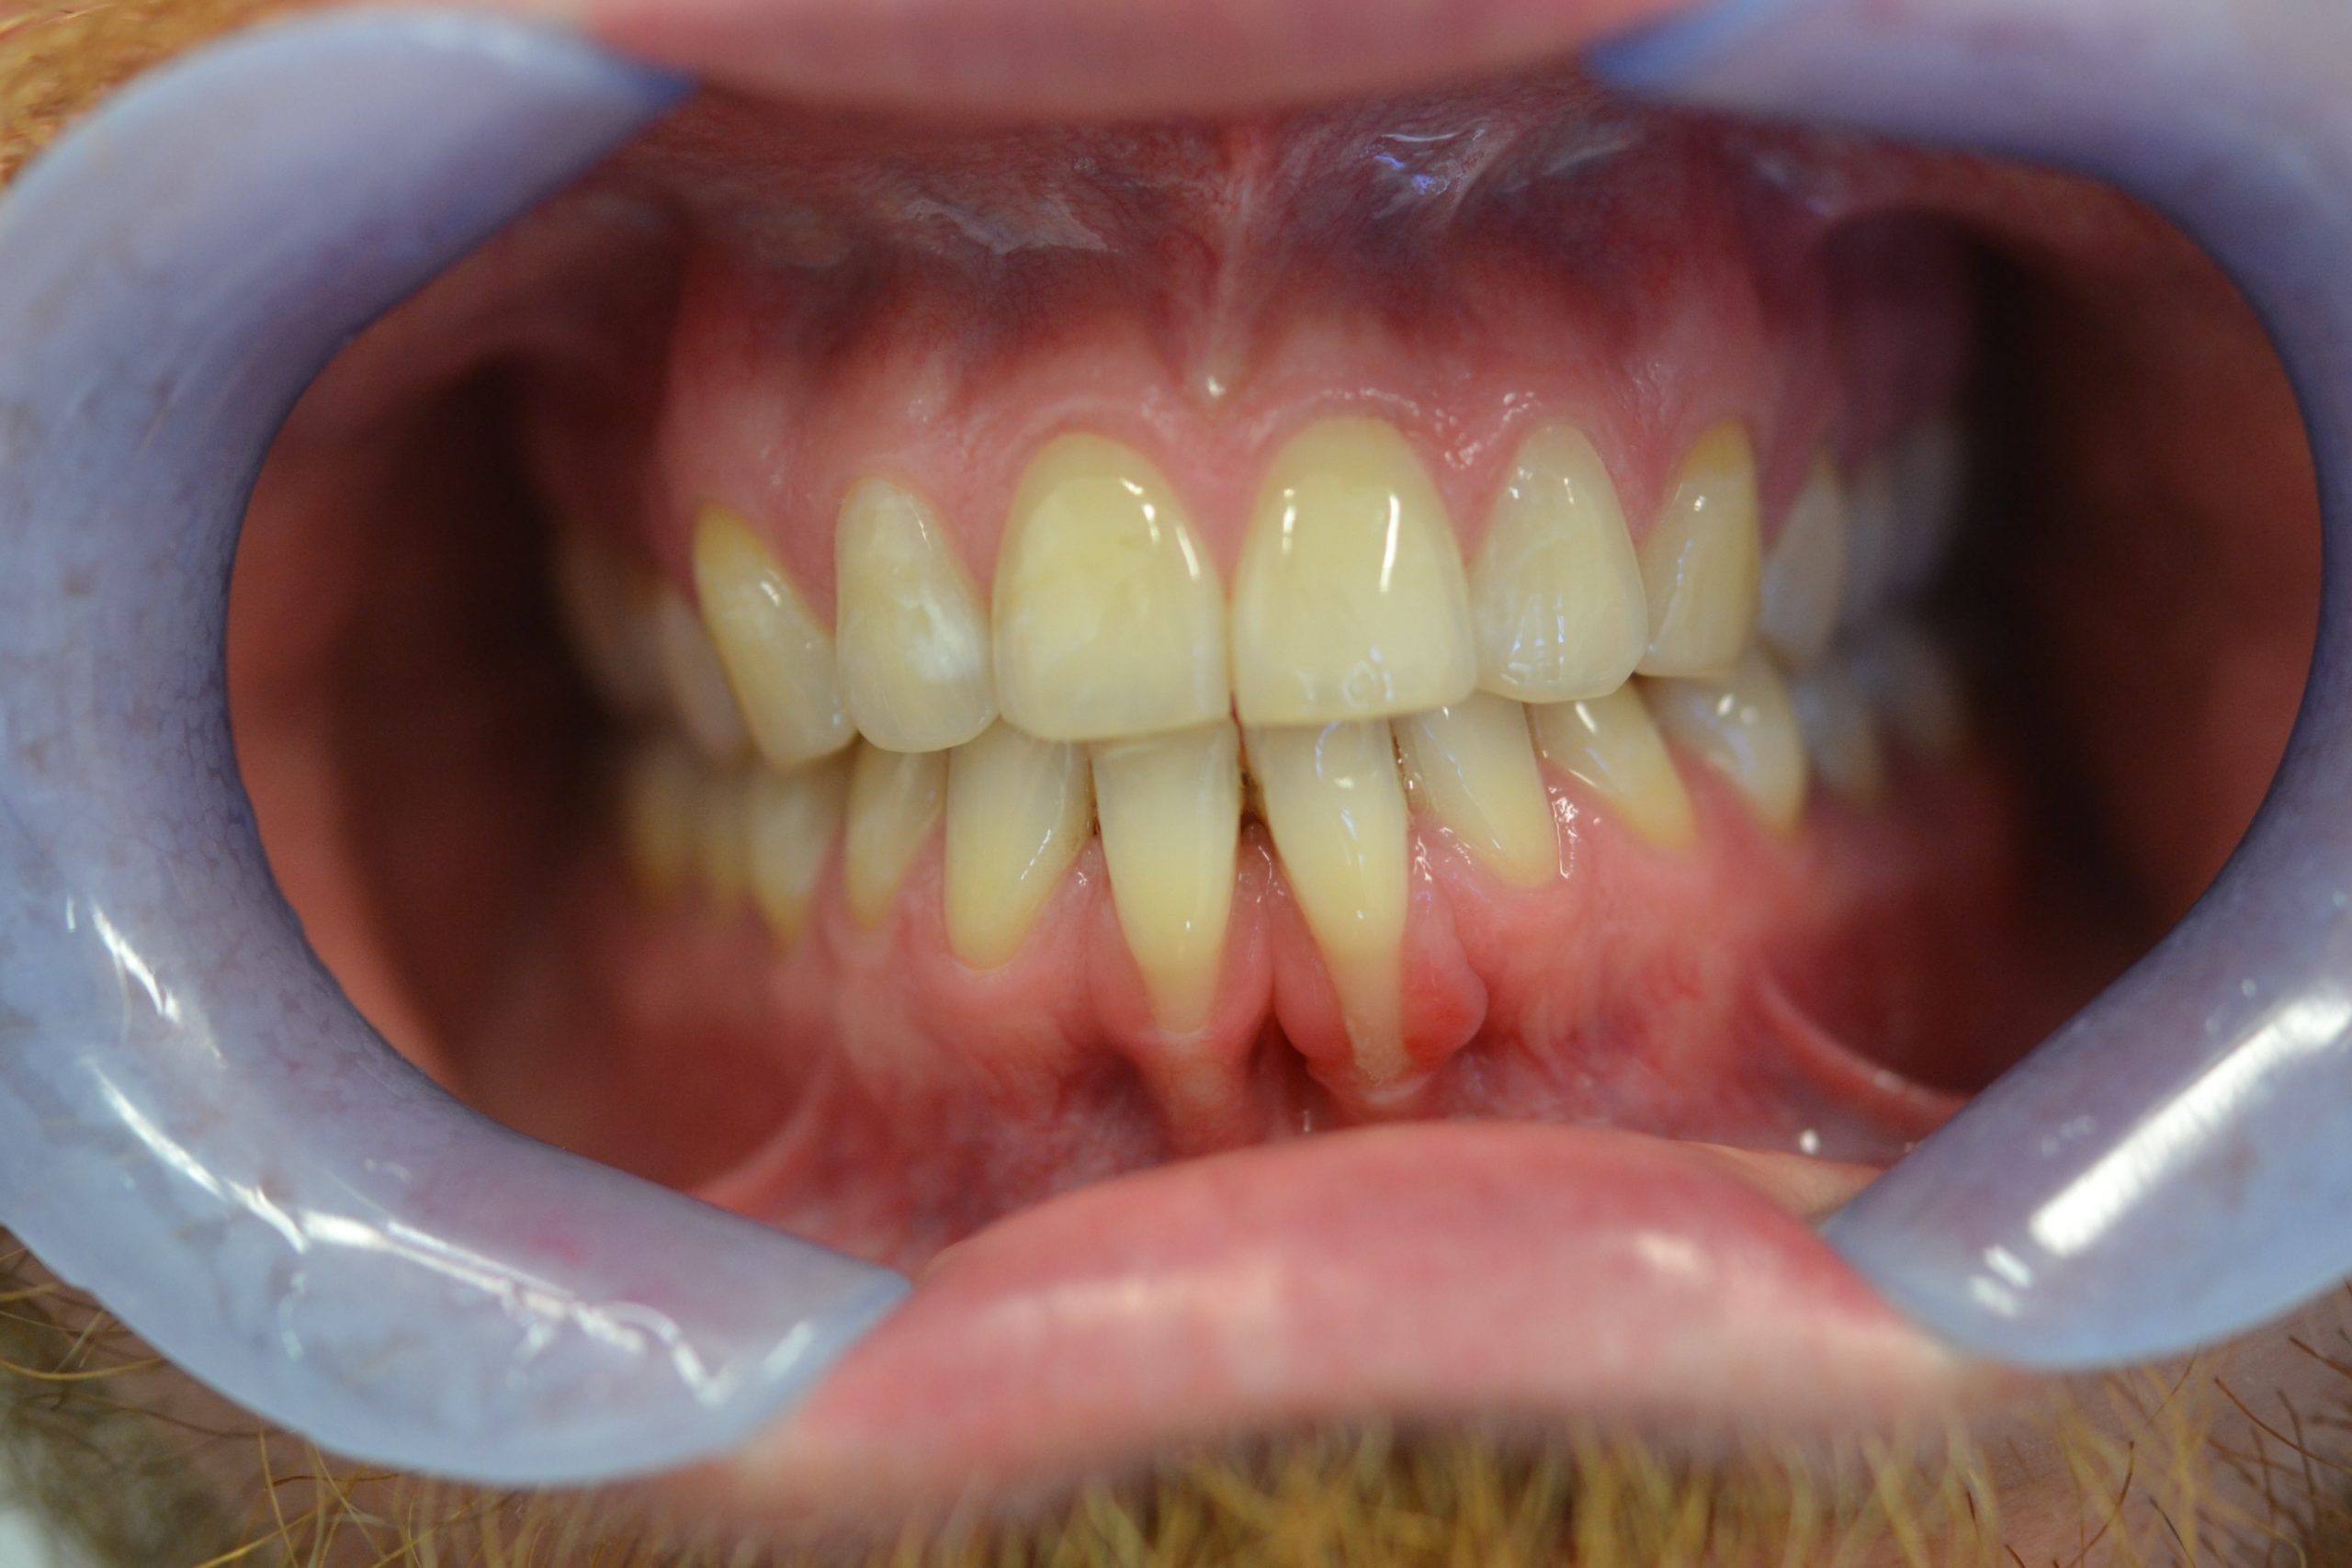

Fallstricke in der Endodontologie

Die endodontische Therapie stellt hohe Anforderungen an Diagnostik, Planung und technische Umsetzung, bietet jedoch bei leitliniengerechtem Vorgehen eine prognostisch günstige und substanzschonende Möglichkeit zum Zahnerhalt.…